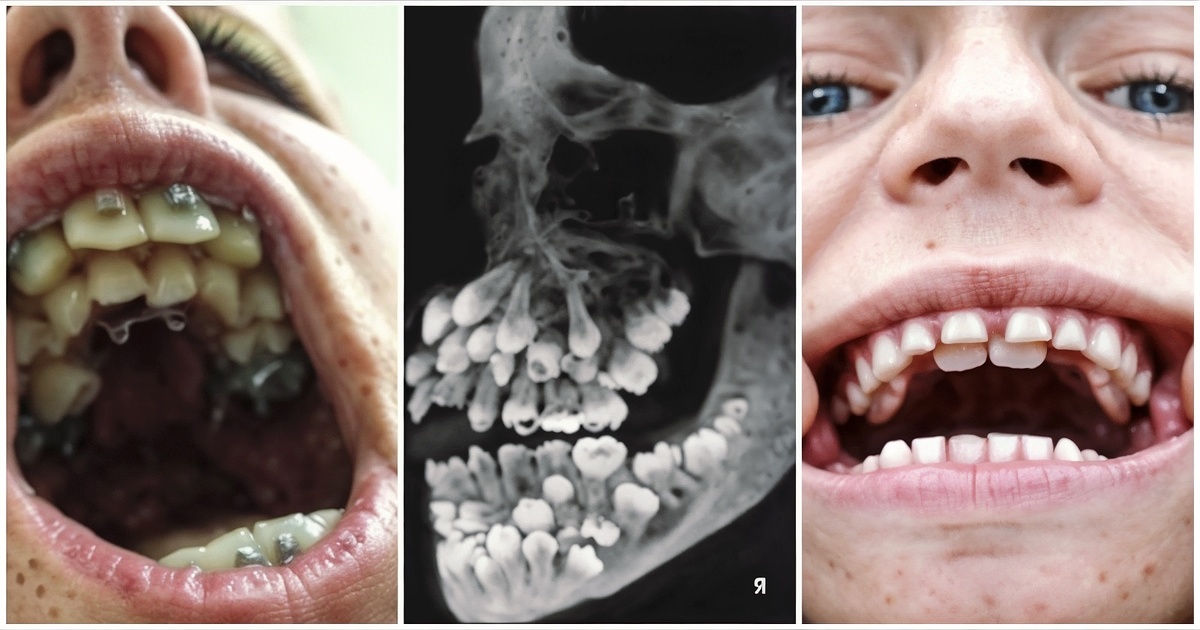

🔹 Факт №2: Зубы растут в несколько рядов , как в лифтовой шахте. Когда передний зуб сломается (например, во время атаки на дельфина), его тут же заменяет следующий.

Факт №2: Зубы растут в несколько рядов , как в лифтовой шахте. Когда передний зуб сломается (например, во время атаки на дельфина), его тут же заменяет следующий.

Факт №3: Ключевой секрет – стволовые клетки , которые у акул остаются активными всю жизнь . Это позволяет их зубам "перезаряжаться" без остановки.